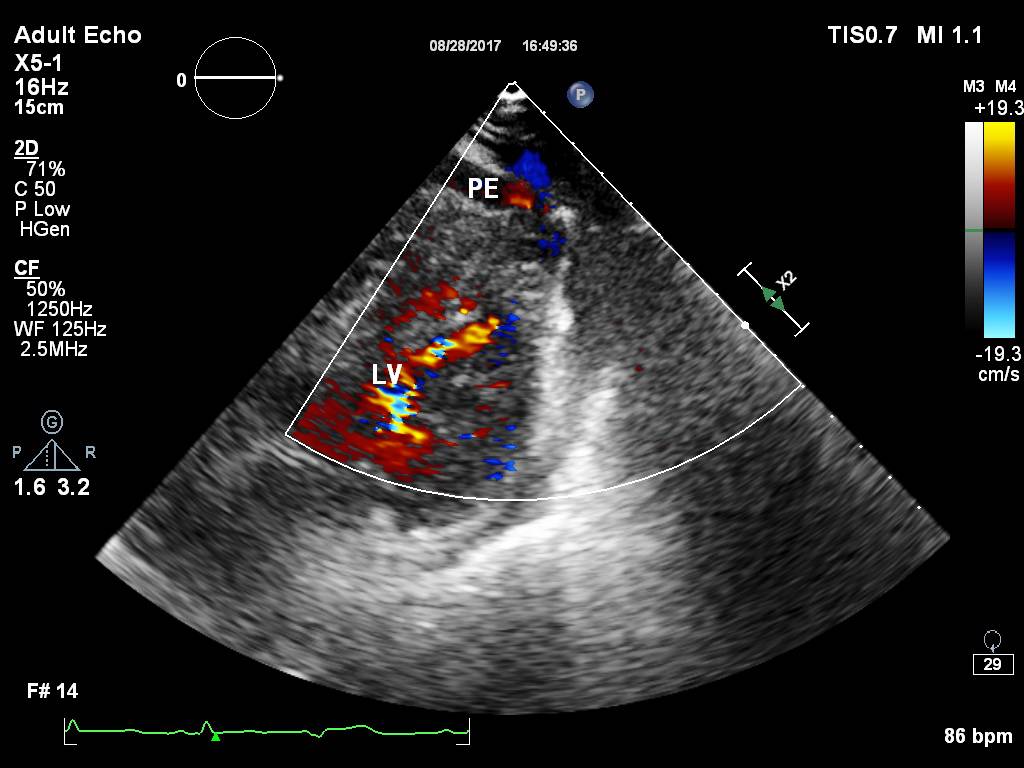

(图1)

(图2)

图1和图2 :术中行心包积液彩超可见:心包腔内见液性暗区:右房顶部  20mm,右室前壁最多时25 mm,右室侧壁旁15 mm。提示:心包积液(中大量)。

图3和图4: 彩色多普勒:心包腔可见可疑的较明亮彩色信号。